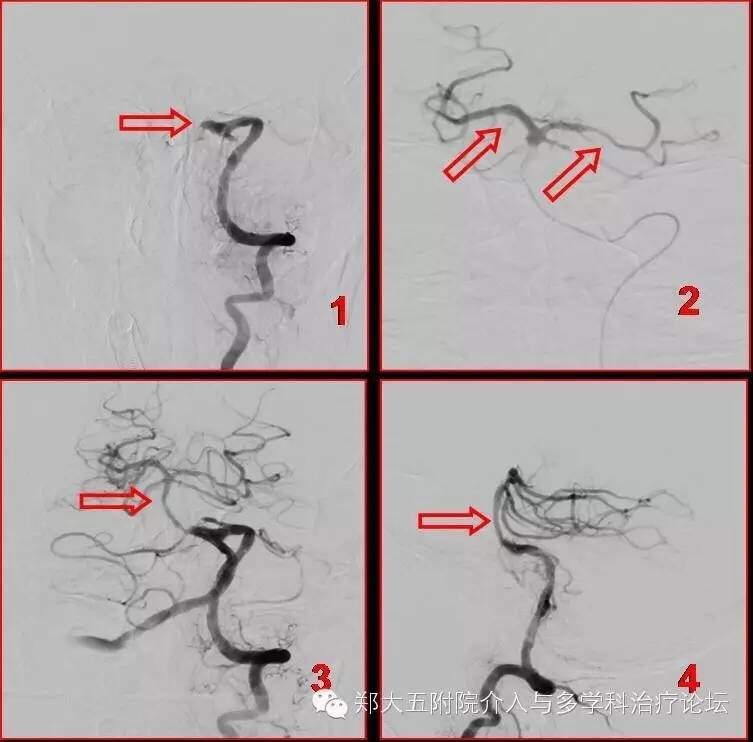

随即,神内一病区、介入病区、导管室、麻醉科,急诊取栓绿色通道无缝衔接,2016年3月17日下午2点,患者被推进寄托生命希望的地方——介入手术室,一场挽救生命的战争悄无声息的展开了,神经内科一病区何远宏主任亲临手术现场指导,介入科吕军主任快速而细致的进行着每一步手术操作,每一分钟、一秒钟对于患者都至关重要,闭塞的血管早开通一分钟甚至都会多挽救出更多的脑组织,导管顺利到位后造影显示与术前MRA一致:患者基底动脉完全闭塞,无任何正向血流通过,毫无间歇,吕军主任随即用微导管及导丝配合小心的一点点通过闭塞的血栓,造影确认后送入专用的取栓装置,顺利取出少量新鲜血栓,再次造影就可见闭塞的血管已有血流通过,这一血流通道毫无疑问打开了生命的另一扇门,让在场的人员看到了新的希望。但患者基底动脉本身有明显狭窄,所以血流仍缓慢。为患者有良好的预后考虑,需对这一部分血管进一步的扩张成形,吕军主任就选择一个小的球囊对狭窄血管进行扩张,扩张后又在病变血管部位植入一枚支架,再次造影后可以看到血管通畅,血流明显改善。

图解:图1 造影显示基底动脉近端血栓堵塞血管(图1红箭),远端血管不显影;图2 导丝导管配合通过血栓后造影显示远端双侧大脑后动脉血流通畅(图2红箭);图3取栓+球囊扩张+支架植入术后正位造影显示基底动脉血流通畅(图3红箭);图4取栓+球囊扩张+支架植入术后正位造影显示基底动脉血流通畅(图4红箭);